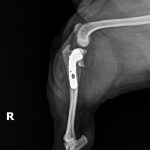

チワワ(6kg)の左前十字靭帯断裂に対するTPLO術(脛骨高平部水平化骨切術)☑